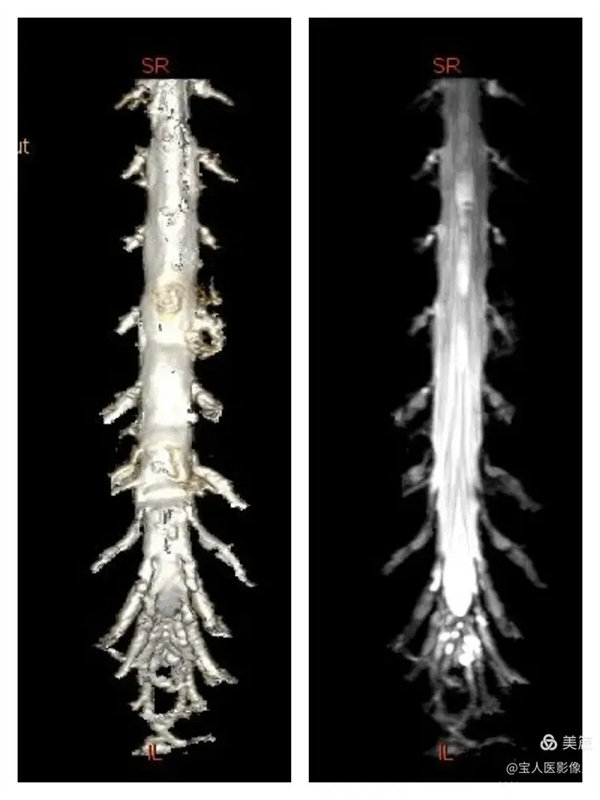

容積成像和最大密度,顯示腰段腦脊液正面圖。

最大密度正面圖,顯示腰段腦脊液(高信號),其內的馬尾神經以及腰神經(線狀稍低信號)。